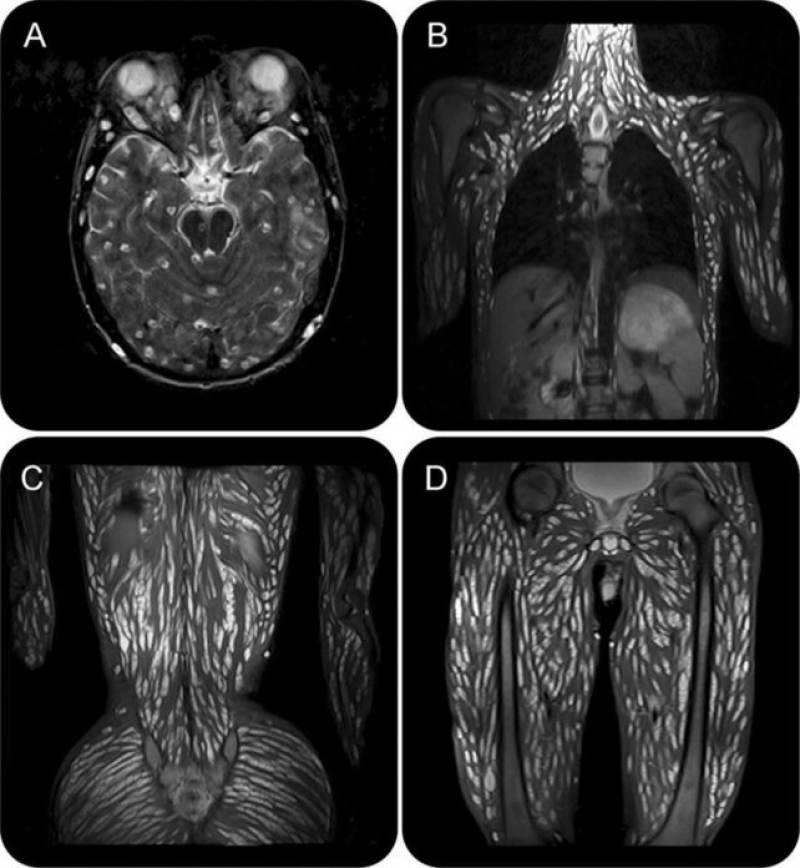

โดยระบุว่า จากภาพนี้จะเห็นจุดสีขาวๆ ซึ่งเป็นระยะตัวอ่อน cysticercus ของพยาธิตืดหมู กระจายเต็มไปหมด ผู้ป่วยอายุ 18 ปี ไปโรงพยาบาลด้วยอาการปวดศีรษะอาเจียน ชัก และประสาทสัมผัสที่เปลี่ยนแปลง

แพทย์ตรวจ MRI พบซีสต์จำนวนมากในเนื้อเยื่อสมอง ศีรษะ กล้ามเนื้อ คอ ผนังหน้าอก ผนังหน้าท้อง กล้ามเนื้อข้างกระดูกสันหลัง สะโพก กระดูกเชิงกราน และกล้ามเนื้อแขนขา